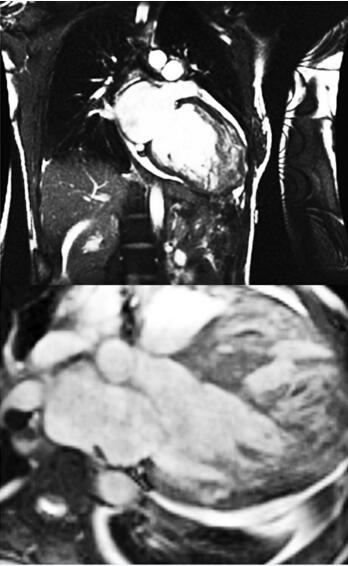

入院后诊治经过:患者收入CCU后,入院查血气分析提示低氧血症。床边胸片提示肺水肿。立即给予吸氧、心电监护,给予强心、利尿、扩血管、解痉平喘等治疗3天后症状缓解,夜间能平卧,两肺干湿啰音消失。入院后复查心脏彩超提示:主动脉根部内径33mm、左房内径45mm、左室舒张末内径59mm、室间隔10mm、左室后壁10mm,LVEF34%,二、三尖瓣中度反流。左室心尖部、前侧壁心内膜面探及多发性突入左室腔内的肌小梁,小梁之间可见深度不同的间隙,病变均累及左室游离壁的中下部,以心尖部及前侧壁为著。室间隔基本正常(图8-4-1)。MRI:左室舒张末期横径58.7mm,侧壁厚度13mm,室间隔厚度10mm,LVEF 37.2%。左室心肌存在增多粗乱肌小梁,肌小梁间可见深陷隐窝,肌小梁间隐窝与左室腔交通(图8-4-2);次日至导管室行冠状动脉造影示:左右冠状动脉均正常。综合入院后多项检查结果我们排除了冠心病、高血压性心脏病、风湿性心脏病以及心包积液等疾病,本病例科内讨论后我们考虑本病系心室肌致密化不全(NVM)引起。患者入院治疗后症状缓解,10天后出院,出院后带药:改善心室重构(培哚普利,4mg每日1次;美托洛尔6.25mg,每日2次);利尿药:氢氯噻嗪25mg,隔日1次;螺内酯20mg,隔日1次;强心药:地高辛0.125mg,每日1次;抗凝药:华法林3mg每日1次。

8-4-2 上图为冠状面、下图为矢状面。可见左房、左室扩大,左室内肌小梁增粗,加深